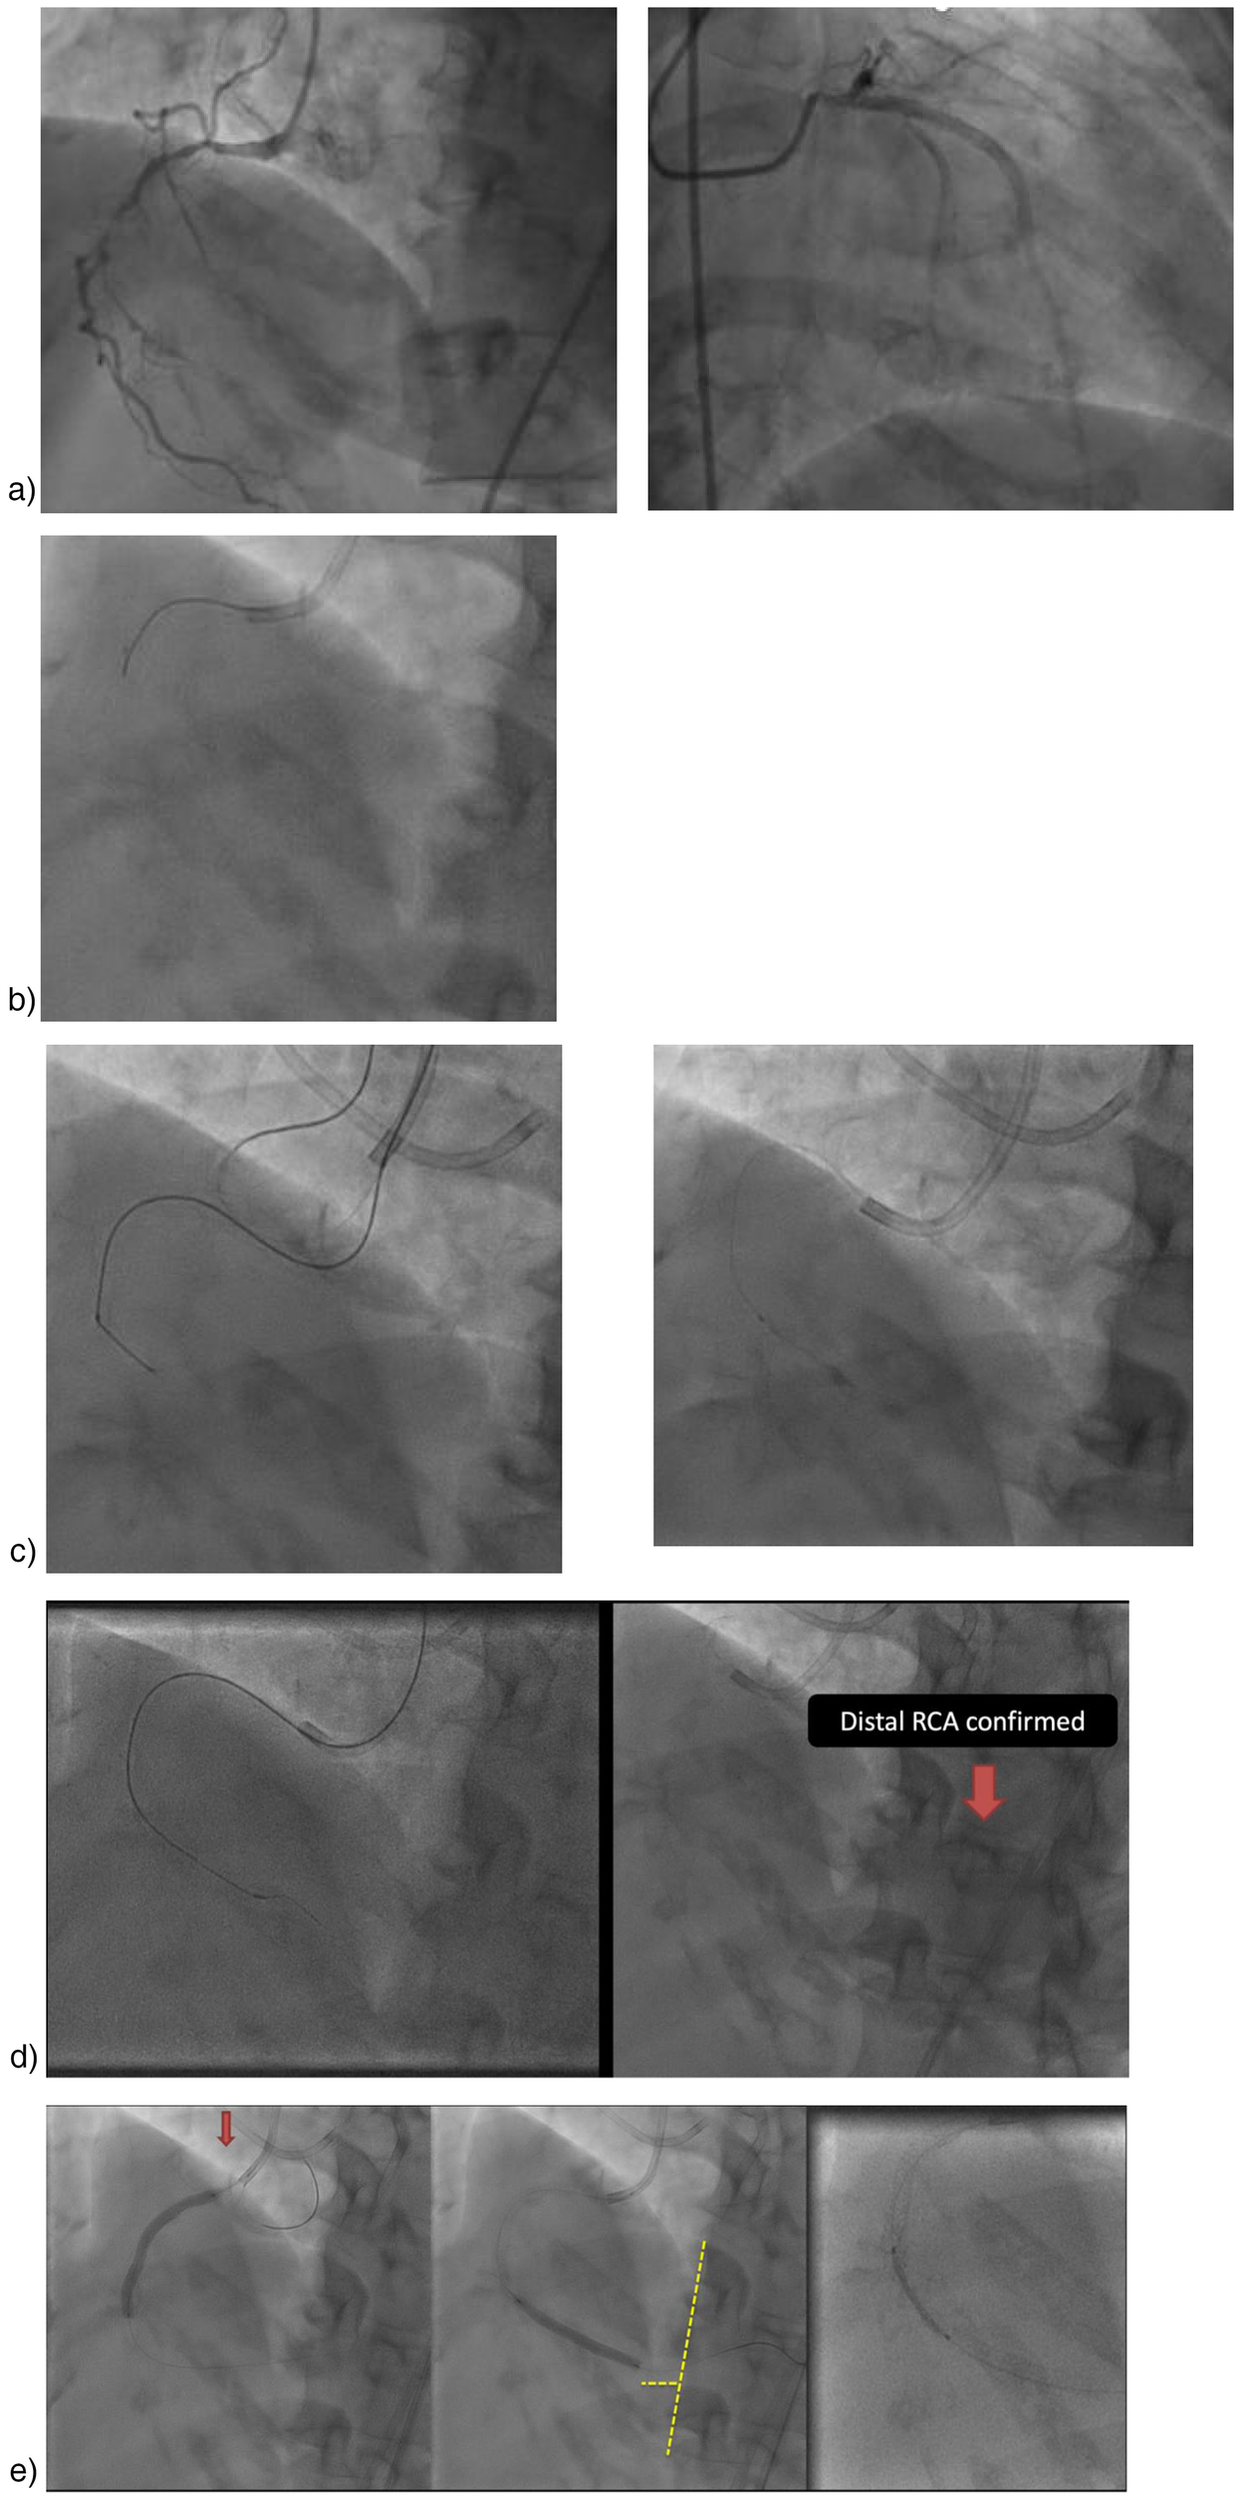

We opted for treatment using ultra-low contrast PCI with “microcatheter injection” technique to address the presence of chronic total occlusion (CTO) and minimize contrast use (see Figure 1a). Right coronary artery (RCA) cannulation was performed using a Judkins Right 3.5/7F catheter, assisted by Finecross 1.8F microcatheter. The microcatheter was placed prior to the lesion before contrast injection. We injected 10–20 ml of 0.9% saline through the catheter and the amplitude of the T-wave inversion increased. Then, runthrough NS floppy coronary wire was inserted. A hand injection of 0.5 cc of contrast confirmed total occlusion in the proximal segment (see Figure 1b). The coronary wire was anchored to the conus branch. Subsequently, an escalation wire (Fielder XT), was utilized to penetrate the lesion and was positioned distally with the backup microcatheter. After removing the wire, another hand injection of 0.5 cc of contrast was performed to verify that the microcatheter was within the RCA lumen (see Figures 1c,d). Predilatation was conducted multiple times with Sapphire balloons measuring 2.0 × 15 mm and 3.0 × 15 mm, advancing from the proximal to the distal segment.

Figure 1

Ultra-Low contrast PCI with microcatheter injection. (a) Initial angiography (3 months earlier), (b) Cannulation and then using saline 10–20 cc and 0.5 cc contrast, (c) A Judkins left catheter can be seen in addition to the right catheter, used to confirm the position of the contralateral wire, if needed. Injections were only made through the right microcatheter. Wiring using Fielder XTA, and confirmed with 0.5 cc contrast for confirmation stump, (d) Micro tip injection, (e) Stent placement.

An anatomical marking technique was employed for the placement of both the distal and proximal landing zones. For the distal landing zone we utilized vertebrae as landmarks, while the proximal landing zone was guided by positioning an additional wire in the conus, allowing precise identification of the ostial location. A drug-eluting stent (DES) Promus Premiere 3.5 × 38 mm was implanted from the ostium to the mid segment, followed by the implantation of a mid to distal DES Xience Xpedition 3.0 × 38 mm. Balloon measurement was performed to ascertain the length of the DES in the mid region by evaluating the gap between the previously placed stents. Subsequently, a third DES Promus Premiere 3.5 × 16 mm was implanted in the mid-right coronary artery (RCA) (see Figure 1E). Angiographic evaluation was conducted using a hand injection of 0.5 cc of contrast (Figure 2), with the total contrast volume utilized during the procedure being only 5 cc. At one-year follow-up, our patient demonstrated a significant improvement in left ventricular ejection fraction (LVEF), increasing from 33% to 56%. Additionally, her symptoms resolved, with no reported chest pain. This patient showed no AKI. There was no significant decline in renal function, as the serum creatinine increased only slightly from 1.59 to 1.61 mg/dl and the estimated glomerular filtration rate (eGFR) decreased minimally from 39 to 38 ml/min/1.73 m2 over 72 h.